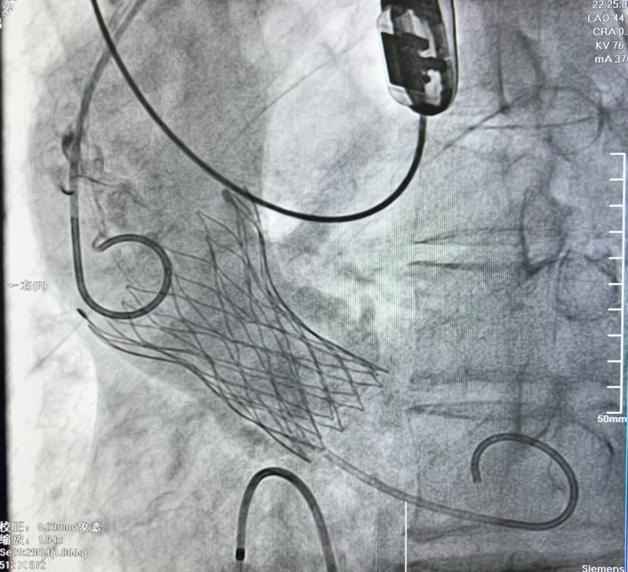

患者之二为71岁男性,近10天来间断胸闷不适,既往有血压升高史,来院就诊胸部CT提示心影增大,心电图显示窦性心律、ST改变,心脏超声提示主动脉瓣二叶瓣畸形,伴重度钙化及狭窄,左室壁增厚,左心收缩功能减退,跨瓣压差107mmHg。入院诊断主动脉瓣重度狭窄、慢性心功能不全急性加重、心功能II--III级(NYHA分级)顺利植入TaurusElite AV26瓣膜术后超声结果显示跨瓣压差降至8mmHg,手术取得圆满成功。

病例1:重度主动脉瓣关闭不全瓣膜植入      病例2:重度主动脉瓣狭窄瓣膜植入